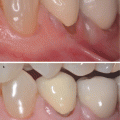

Alveolar crest-cementoenamel junction relationship (Fig. 5.2) – this can be divided in subtype A (where the distance between these structures is around 1.5 mm, and a normal attachment of gingival fibers into the cementum is observed) or subtype B (both structures are at the same level) [8].

Fig. 5.2

(a–d) Alveolar crest–cementoenamel junction relationship. Subtype A – the distance between these structures is around 1.5 mm, and a normal attachment of gingival fibers into the cementum is observed (a, b). Subtype B – both structures are at the same level (c, d)